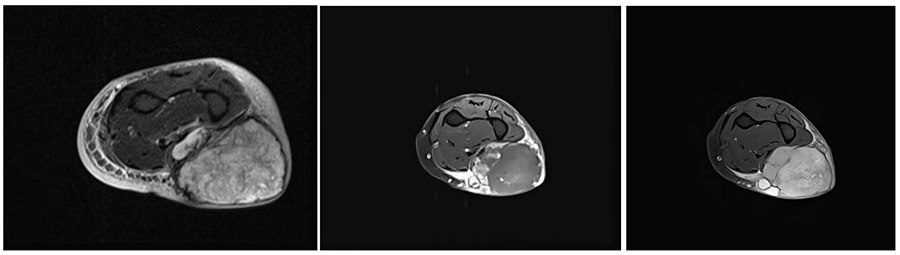

Ameliyat Öncesi: MR’da ön kol yerleşimli sınırları düzensiz, heterojen görünümlü yumuşak doku tümörü görülmekte